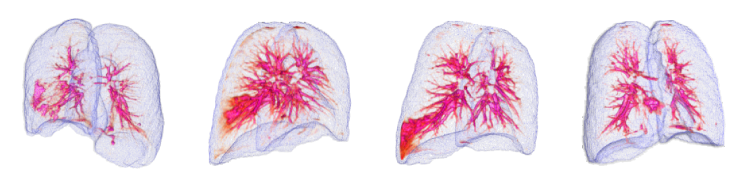

By using the internal clinical dataset from SMC of pneumonia and tuberculosis cases, we experimentally verified the superiority of the proposed VMPR-UAD through various comparative experiments. We also provide quantitative results and 3D abnormal (lesion) localization/visualization results of VMPR-UAD using the internal dataset for pneumonia and tuberculosis in the Supplementary Material to illustrate the superiority of anomaly localization by VMPR-UAD.

3.4.1 Performance of VMPR-UAD and SL method

The proposed VMPR-UAD only requires data from healthy subjects for network training. To compare the VMPR-UAD with an SL method that requires training data from both healthy subjects and patients showing anomalies, the SL method was trained as follows. We set the number of training samples to the maximum possible, with the ratio of normal to abnormal cases being 1:1, and fivefold Monte Carlo validation was adopted during SL training. We randomly selected 450 normal, 350 pneumonia, and 100 tuberculosis cases for training. For pneumonia detection using the SL method, 350 of the remaining stacks from healthy subjects were randomly selected along with 350 stacks showing pneumonia. For tuberculosis detection, 100 stacks from healthy subjects were randomly selected along with the 100 stacks showing tuberculosis. For detection of both diseases, 450 stacks from healthy subjects were randomly selected along with the 350 and 100 stacks showing pneumonia and tuberculosis, respectively. For the SL network, we adopted a 3D convolutional neural network, 3D-ResNet18 [40], with the 3D stack of original CT slices as its input. The results of comparing the SL method with the proposed VMPR-UAD are listed in Table C and shown in Fig. G. The proposed VMPR-UAD shows higher performance in anomaly detection by improving the AUC by more than 10%, despite only using data from healthy subjects for training. This result confirms the superiority and convenience of our proposal over an SL-based diagnosis, especially when the training data of the target disease are insufficient or difficult to distinguish and annotate.